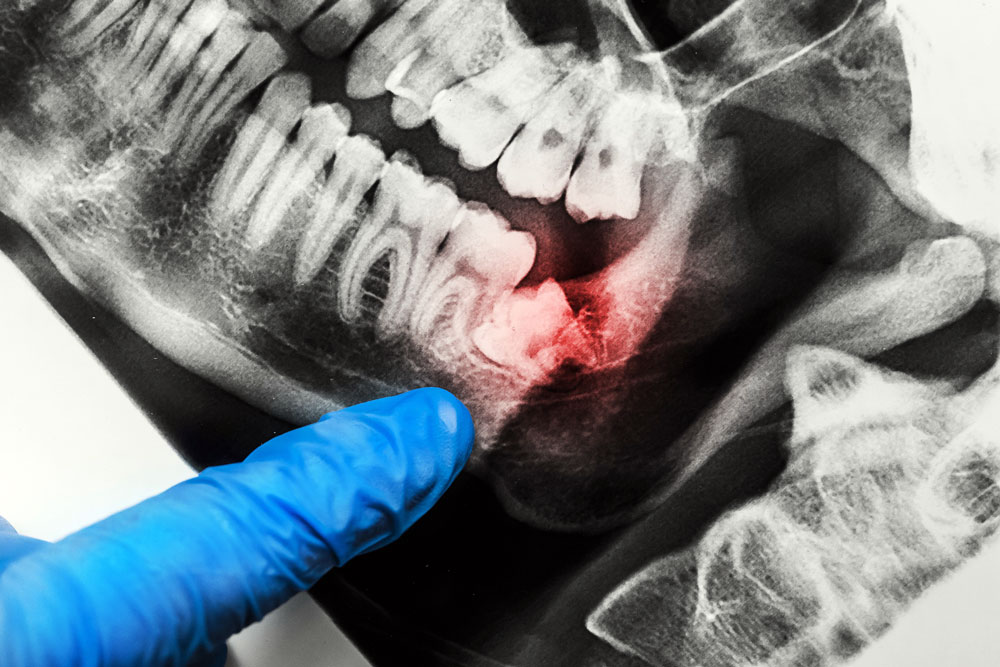

Tooth Extraction Including Wisdom Teeth

If you require an extraction, our experienced team uses proven techniques for routine or complex extractions as well as wisdom teeth removal.

Our principal dentist Dr Shaibani has a special interest in surgical procedures with a vast knowledge and experience in both simple and surgical extraction of teeth and wisdom teeth alike.